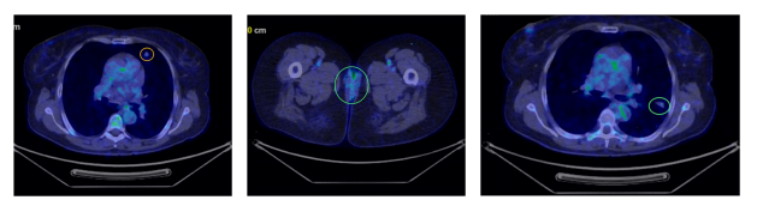

术后5个月PET-CT显示双肺多发非钙化小结节,代谢轻度增高,提示转移(图1)。

图1 首次PET-CT显示双肺多发非钙化性结节(以黄色和绿色圆圈标出)

术后6个月PET-CT示肺结节

数量、大小及代谢均进一步增加,最大约 28 × 20 mm(图2)。穿刺活检:PAX8(+)、CD10(+)、CK7(–)、S100(–)、Ki-67 15–20%。

图2 第二次PET-CT扫描显示肺部病灶进展(以箭头标示)